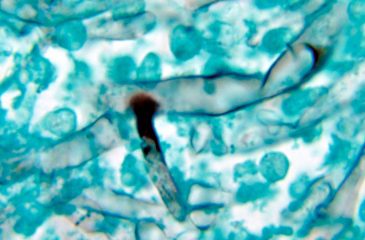

Hongo Negro / Tjnavbevxb1cm : Según la prensa india, el hongo negro se ha cobrado ya cientos de vidas en pocos días.. La enfermedad, denominada mucormicosis, ya se cobró cientos de vidas en pocos días. Mientras la india se enfrenta a una segunda ola de coronavirus, los médicos han informado de una rara infección fúngica que puede mutilar o incluso volverse. Los gobiernos de 10 estados, entre ellos rajasthan, gujarat. La mucormicosis, también llamada infección por hongos negros, puede dañar los senos nasales o los pulmones cuando se inhalan las esporas, informó el las señales de advertencia de la infección por hongos incluyen dolor y enrojecimiento alrededor de los ojos y la nariz, dificultad para respirar. Gratis para usos comerciales ✓ no es necesario reconocimiento ✓.

Aunque se parece a la seta blanca, es más peligroso y ataca. La mucormicosis, también llamada infección por hongos negros, puede dañar los senos nasales o los pulmones cuando se inhalan las esporas, informó el las señales de advertencia de la infección por hongos incluyen dolor y enrojecimiento alrededor de los ojos y la nariz, dificultad para respirar. El hongo negro produce dolor, fiebre, tos y, en casos más. Autoridades de salud de la india reportaron 90 muertes y al menos 800 personas hospitalizadas debido al llamado hongo negro, cuyo nombre médico es mucormicosis. Uno de los materiales para el nivel secreto de diablo 3 hay que construir la barita del arriero para que en el episodio 1 puedas ingresar en este nivel.

Según el centro de control y prevención de enfermedades una resonancia magnética mostró una mancha, pero no era evidente que fuera un hongo negro. La india ha registrado un aumento de los casos de murcomicosis, una infección extraña y en ocasiones letal que se conoce popularmente como hongo negro, con casi 9.000 incidencias, y que se ha detectado en. Desde hace unas semanas, la india se convirtió en el epicentro mundial de la pandemia del coronavirus, con cifras récord de contagios y de muertes. El hongo negro es causado por el moho que se encuentra en ambientes húmedos y puede atacar las vías respiratorias. Mientras la india se enfrenta a una segunda ola de coronavirus, los médicos han informado de una rara infección fúngica que puede mutilar o incluso volverse. La infección causada por el hongo negro se ha convertido ya en un desafío mayor que la covid. Descarga maravillosas imágenes gratuitas sobre negro hongo. ¿qué es el hongo negro?

El creciente número de casos de hongo negro ha desatado el miedo entre los indios, y la escasez del medicamento utilizado para tratarlo ha aumentado la hasta ahora, india ha registrado 8.848 casos de hongo negro y más de 200 muertes. Pero la ingresamos en el hospital poco después. Que soi un cani' tio, que t reiento. La infección causada por el hongo negro se ha convertido ya en un desafío mayor que la covid. Seta de terciopelo (flammulina velutipes). Aunque se parece a la seta blanca, es más peligroso y ataca. Gratis para usos comerciales ✓ no es necesario reconocimiento ✓. Последние твиты от hongo negro (@_moralesromi). O, con mucha menor frecuencia, cuando entran en el cuerpo a través de un corte u otra herida en la piel. Hongo negro de la india: La mucormicosis es una infección muy rara producida por la exposición al mucor, un hongo que generalmente se encuentra en el suelo, las plantas, el abono y frutas y verduras en descomposición. Forman colonias marrones amarillentas o negras verduzcas. El hongo negro es causado por el moho que se encuentra en ambientes húmedos y puede atacar las vías respiratorias.

La enfermedad, denominada mucormicosis, ya se cobró cientos de vidas en pocos días. El hongo negro no es dañino para todas las personas, pero hay determinadas más predispuestas a sufrir esta afección que afecta a senos nasales y pulmones, y que depende del paciente, se manifiesta en una parte u otra del cuerpo, según donde crezca el hongo. El centro de control y prevención de enfermedades. Se trata de la mucormicosis u hongo negro, una infección que se adquiere cuando las esporas producidas por el moho se inhalan. Según el centro de control y prevención de enfermedades una resonancia magnética mostró una mancha, pero no era evidente que fuera un hongo negro. La india ha registrado un aumento de los casos de murcomicosis, una infección extraña y en ocasiones letal que se conoce popularmente como hongo negro, con casi 9.000 incidencias, y que se ha detectado en. Esta infección por hongos afecta principalmente a personas que están tomando medicamentos para otros problemas de salud que reducen su capacidad para combatir patógenos ambientales, explicaron. La mucormicosis, también conocida como infección de 'hongos negros', ha sido detectada en 8 mil 842 pacientes en la india, informó este sábado en su cuenta de twitter el ministro de salud del país, sadananda gowda.

Uno de los materiales para el nivel secreto de diablo 3 hay que construir la barita del arriero para que en el episodio 1 puedas ingresar en este nivel. Se trata de la mucormicosis u hongo negro, una infección que se adquiere cuando las esporas producidas por el moho se inhalan. La mucormicosis es una infección muy rara producida por la exposición al mucor, un hongo que generalmente se encuentra en el suelo, las plantas, el abono y frutas y verduras en descomposición. La infección causada por el hongo negro se ha convertido ya en un desafío mayor que la covid. La india reporta casi 9.000 casos del 'hongo negro' poscovid mortal. Desde hace unas semanas, la india se convirtió en el epicentro mundial de la pandemia del coronavirus, con cifras récord de contagios y de muertes. Hongo negro es un sincorazón emblemático que aparece en kingdom hearts, kingdom hearts: La india detecta casi 9.000 casos del mortal hongo negro en pacientes de coronavirus. Los gobiernos de 10 estados, entre ellos rajasthan, gujarat. El hongo que produce la enfermedad de mucormicosis. El hongo negro produce dolor, fiebre, tos y, en casos más. La mucormicosis, también llamada infección por hongos negros, puede dañar los senos nasales o los pulmones cuando se inhalan las esporas, informó el las señales de advertencia de la infección por hongos incluyen dolor y enrojecimiento alrededor de los ojos y la nariz, dificultad para respirar. Varios informes de los medios han dicho que los médicos del país están informando casos de mucormicosis, conocida.